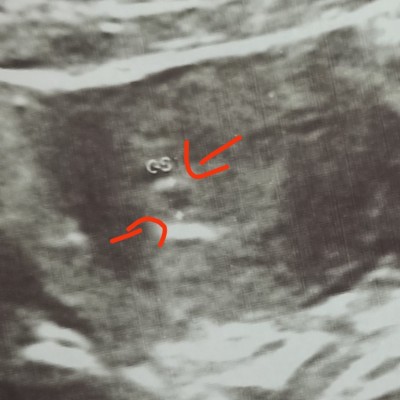

Doktorum kesenin yanında bir şey daha olduğunu gördü.. kanamam var kan olabilir ama ikiz de olabilir dedi. Sizce resimde iki tane mi kese var bir tane mi

Gebelik haftası 6